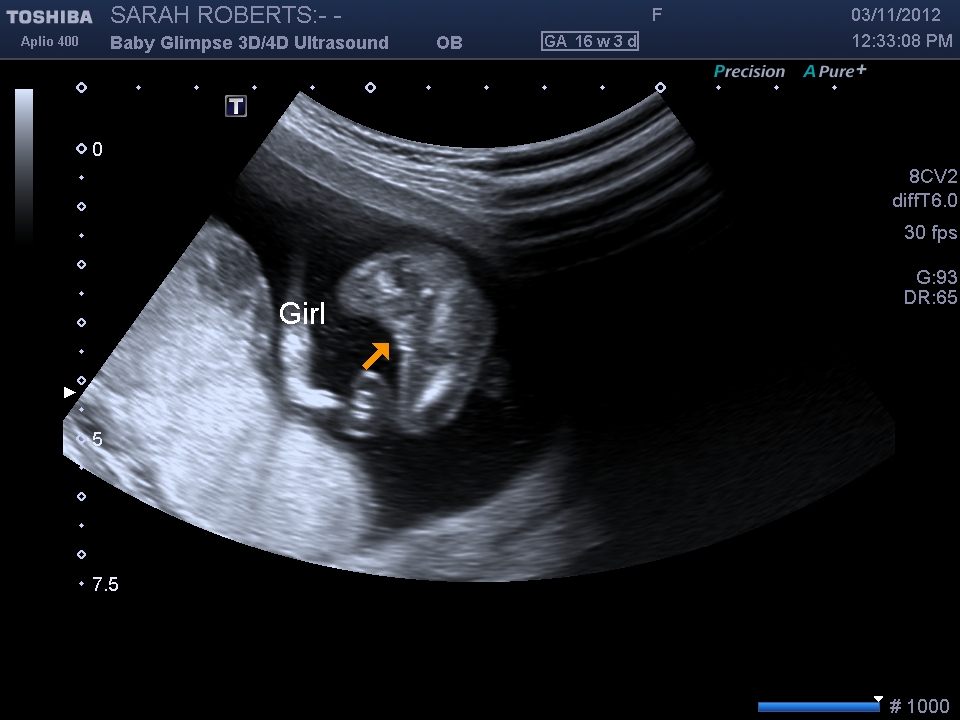

I can't believe it.... We are having a :babyf:!! Attachment 5892 The 12wk nub was a tricky one:wink: